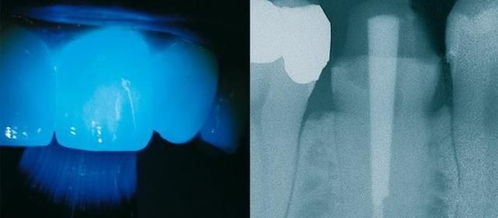

牙齒打樁指在牙齒缺損較大,或因?yàn)橥鈧仍蛑皇O卵栏鶗r(shí),因剩下的牙齒過短或力量過于薄弱,不能用修復(fù)體(主要指烤瓷牙)直接修復(fù),需要給牙根里打樁,加固并延長(zhǎng)折斷的牙齒,以使假牙能獲得足夠的力量固定。其過程是:在徹底做過根管治療的牙根里面打個(gè)樁,再用樹脂或金屬恢復(fù)牙冠部分。樁冠是修復(fù)牙齒缺損的最后一個(gè)選擇,如果牙齒缺損過大,不能做樁的話,那就只好拔除了。

什么樣的牙齒狀況需要打樁?1、由于齲壞(蟲牙),外傷等原因造成牙冠大面積缺損者;2、牙齒缺損只剩下牙根,牙根還可以利用殘根(已經(jīng)沒有牙冠)根面達(dá)牙齦下,牙周健康,牙根有足夠的長(zhǎng)度,經(jīng)牙齦切除術(shù)能暴露出根面者;3、錯(cuò)位,扭轉(zhuǎn)牙而沒有條件做正畸治療或非正畸適應(yīng)者;4、畸形牙,直接磨牙固位不良者。